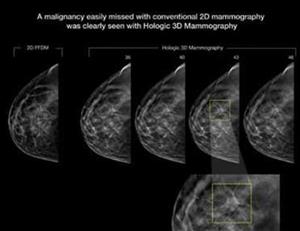

With a continued and dedicated interest in supporting and caring for the women in our community, Sansum Clinic has – with the help of gifts from grateful patient – invested in new 3D Mammography technology, or Breast Tomosynthesis. Our standard 2D digital mammographic imaging has been, and is, an amazing tool for the early detection of cancers. Upgrading to this new 3D technology, the Selenia Dimensions from Hologic®, can help us detect cancers much earlier and those cancers can be caught when they are much smaller, making them easier to treat. A recent article, “Breast Cancer Screening Using Tomosynthesis in Combination with Digital Mammography” from the Journal of the American Medical Association (JAMA, June 25, 2014) highlights the distinct benefit of the technology after a total of 454,850 examinations (281,187 conventional mammograms compared to 173,663 3D mammograms) were conducted. A few of the significant findings are:

• A 41% increase in the detection of invasive breast cancers

• A 29% increase in the detection of all breast cancers

• A 15% decrease in women recalled for additional imaging

An increase in the number of cancers detected is significant and the benefit may seem obvious to those reading this article. Maybe not so obvious in significance is the decrease in the number of women recalled for additional imaging. This means that we can effectively reduce the radiation exposure from additional imaging, and perhaps more importantly, reduce the worry, anxiety and stress among our patients associated with those callbacks.